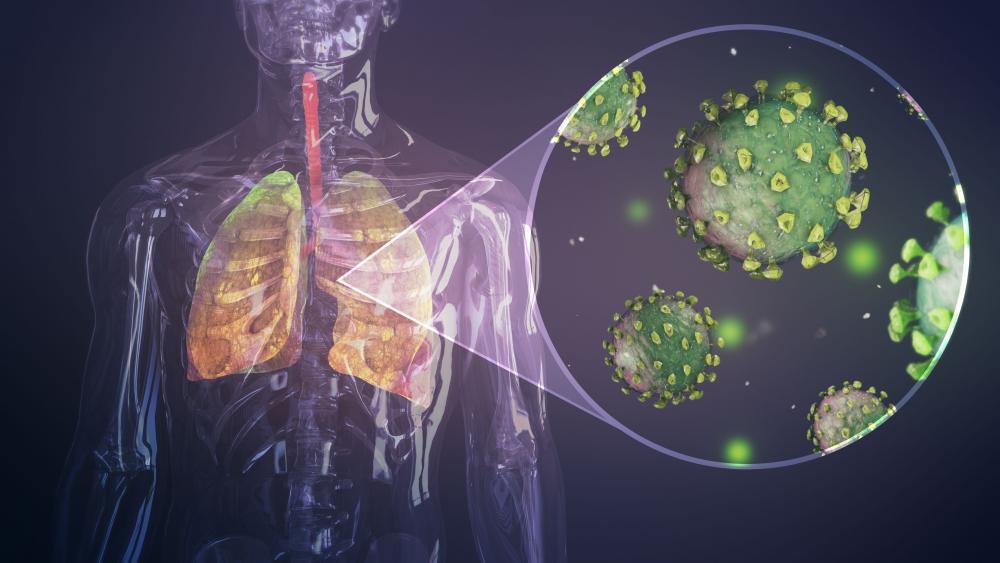

Gli scienziati: “Covid-19 endemico, possibili nuove ondate”

“La probabile traiettoria per il SarsCoV2 è di diventare endemica con dei focolai stagionali a causa della diminuzione dell’immunità naturale, della copertura globale insufficiente dei vaccini e/o dell’emergere di nuove varianti non controllate dai vaccini attuali. Nuove ondate epidemiche sono possibili soprattutto nei paesi con bassa copertura vaccinale“. Lo afferma un panel di 26 scienziati nel rapporto pubblicato sul sito della Commissione Ue in occasione del Global Health Summit di oggi. “Un’equità globale nell’accesso alle risorse“, avvertono, “è sia un imperativo morale che un’esigenza critica per il controllo della pandemia da Covid-19“.